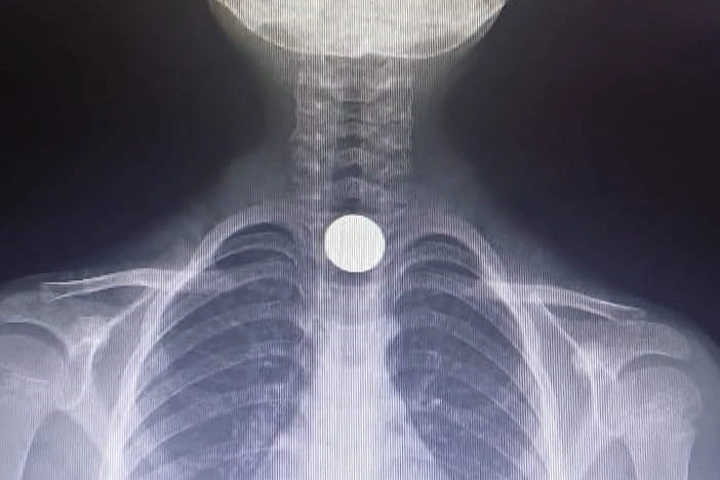

İNEGÖL’DEN BURSA’YA SEVK EDİLDİİnegöl Devlet Hastanesi'nde yapılan tetkiklerde, madeni paranın yemek borusuna takıldığı tespit edildi. Sağlık ekipleri, küçük çocuğun boğazındaki parayı çıkarabilmek için Bursa Yüksek İhtisas Eğitim ve Araştırma Hastanesi'ne sevk etti.